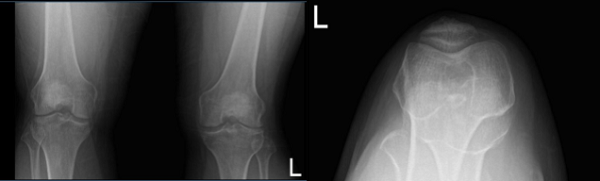

An MRI and X-ray were performed, which shows lateral meniscus tear. We discussed treatment options and the patient opted for surgical management. We discussed the risks and benefits and complications of the surgery. We discussed possible meniscal repair versus meniscectomy. The patient understood and signed an informed consent.